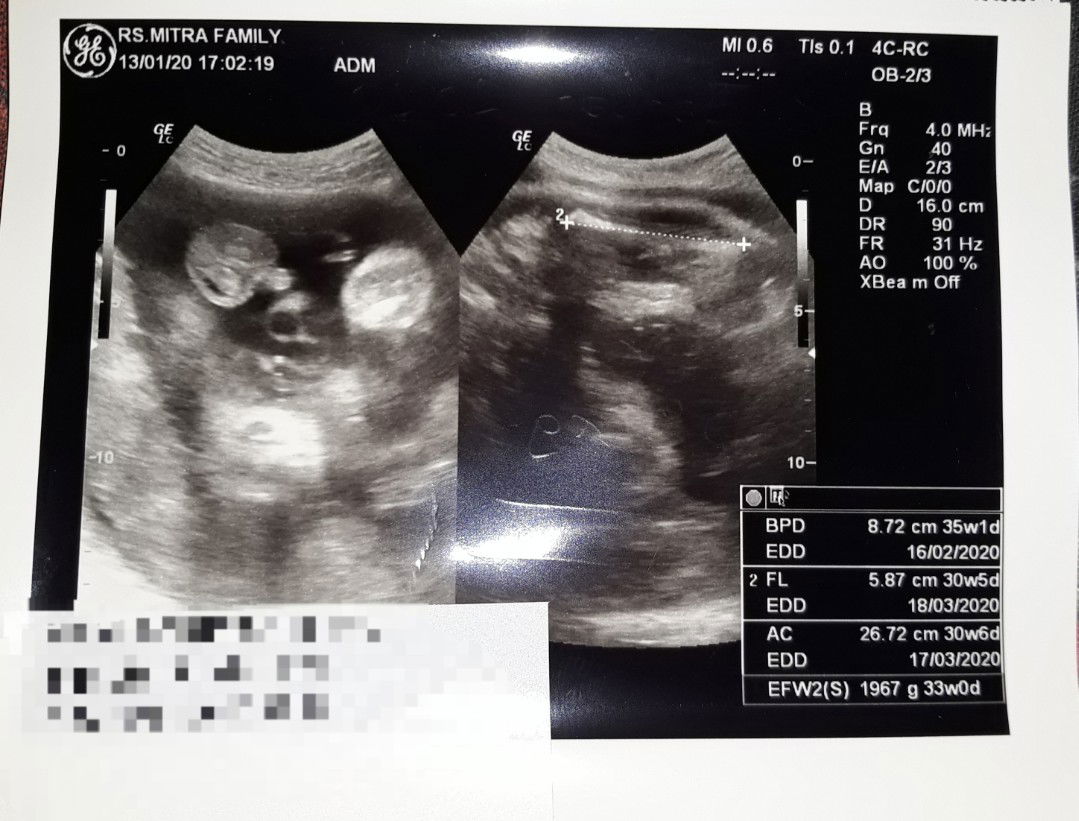

33 Weeks

Kemarin abis usg masuk uk 33 minggu dan alhamdulillahnya kepala udh dibawah dan waktu di usg muka si bayi katanya lagi menghadap depan, meskipun kurang jelas gambarnya ? yg penting kau sehat de